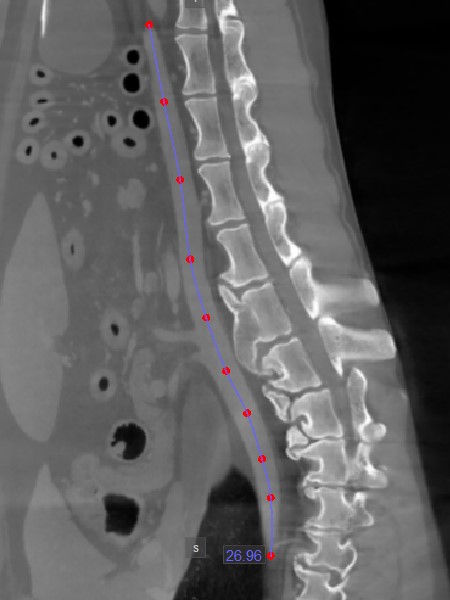

Görbe hossz mérés¶

Az Görbe hossz mérés eszköz lehetővé teszi a felhasználók számára, hogy nem lineáris út mentén mérjék meg görbe vonalak vagy komplex alakzatok körvonalának hosszát.

Válassza ki az Görbe hossz mérés eszközt, és rendelje hozzá az elérhető egérgombok egyikéhez. Indítsa el a mérést az aktív kép egy szeletén, nem lineáris út mentén a pontok elhelyezésével. Ahogy a felhasználó pontokat helyez el, a szoftver automatikusan összeköti őket és létrehozza az útvonalat.

Fejezze be a mérést az útvonal utolsó pontjának elhelyezésekor duplakattintással, vagy használja a jobb egérgombot az útvonal azonnali kiszámításához. Az útvonal hossza megjelenik a mérés mellett.

Az útvonal módosításához mozgassa a formát leíró pontok egyikét a Alapértelmezett eszközzel.